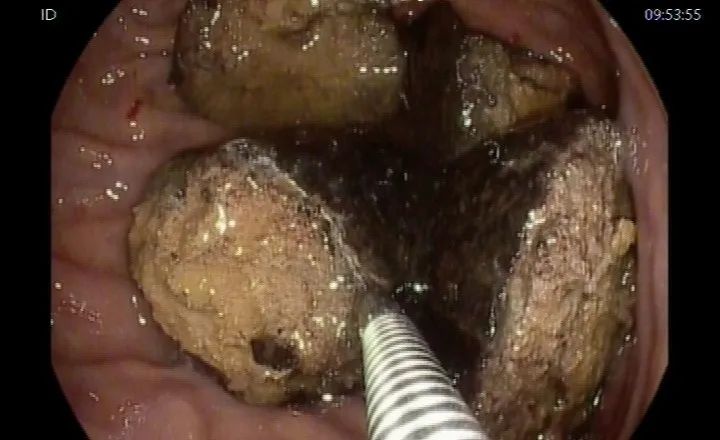

这么大的结石岂不是要“开膛破肚”,看出孙先生担忧的邓主任说:“别担心,不用开刀,我们的胃镜下碎石取石就可以‘干掉’它”。随后,邓冬生主任充分评估病情,给孙先生实施内镜下胃石碎石术,即在胃腔内把结石分块切割、打碎,将分裂的大块结石通过异物钳取出,考虑取石时间太久,患者会产生不适,于是还剩下一些细小的结石并未清理。

术中